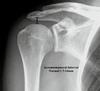

Type I injuries involve purely an AC joint sprain with intact CC ligaments. Type II injuries involve complete tearing of the AC joint and a sprain of the CC ligament with the CC measurement being < 25% greater than of the contralateral shoulder. Type III, IV, V, and VI injuries all involve complete tearing of both the AC and CC ligaments. Type III injuries have a CC distance measurement between 25 and 100% greater than that of the contralateral side (this patient) compared to Type V injuries which have a CC distance > 100% of the contralateral side. Type IV and VI injuries represent posterior and inferior dislocation of the clavicle, respectively. The coracoacromial ligament is generally spared in these injuries